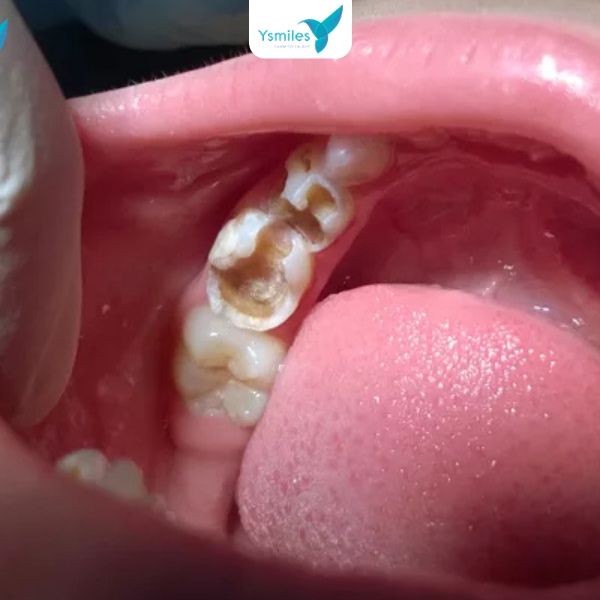

Bài viết hướng dẫn cách điều trị sâu răng cho trẻ em đúng cách, an toàn và phù hợp từng mức độ, đồng thời gợi ý lựa chọn nha khoa uy tín cho bé.

Sâu răng ở trẻ em là vấn đề phổ biến khiến nhiều phụ huynh lo lắng, đặc biệt trong giai đoạn răng sữa phát triển. Điều trị sâu răng sớm không chỉ giúp bé giảm đau nhanh mà còn ngăn ngừa biến chứng ảnh hưởng đến răng vĩnh viễn sau này.

Bài viết dưới đây sẽ bật mí cách điều trị sâu răng cho trẻ em an toàn và hiệu quả, kết hợp giữa chăm sóc tại nhà và can thiệp chuyên khoa, giúp bé giữ nụ cười khỏe mạnh mỗi ngày.

Cách điều trị sâu răng cho trẻ em hiệu quả

Điều trị sâu răng cần phân loại theo mức độ như nhẹ (đốm đen bề mặt), trung bình (lỗ sâu men) đến nặng (lan đến tủy). Phát hiện sớm giúp việc điều trị sâu răng đơn giản hơn, tránh nhổ các răng không cần thiết.

Răng sữa bị sâu ở trẻ nhỏ hiện nay khá phổ biến do bánh kẹo và nhiều nguồn thức ăn khác